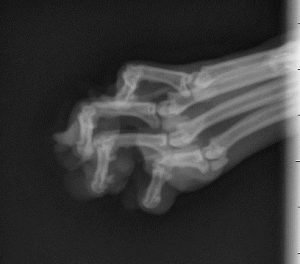

OzminXray